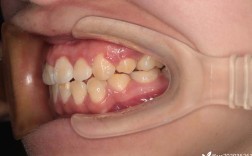

牙齿矫正失败图曝光,这些失败案例究竟为何发生?

我理解你想了解牙齿矫正失败的具体案例图片,但需要明确几点重要信息:无法提供真实患者图片:出于患者隐私保护和医学伦理的考虑,我不能直接展示真实的、可识别身份的患者牙齿矫正失败照片,这些图片属于患者的个人医疗信息,“失败”定义复杂:牙齿矫正...